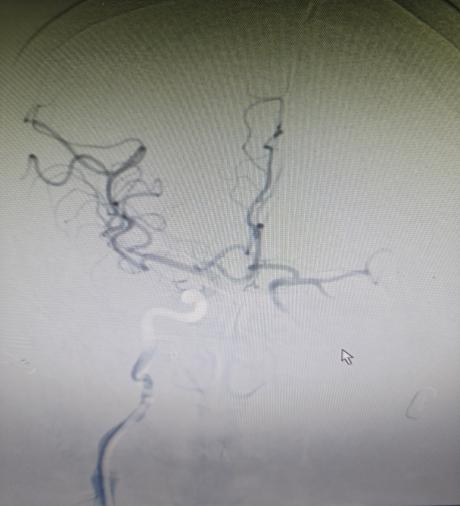

“时间就是大脑,每延迟一分钟,就有190万个神经细胞不可逆坏死!”面对紧急病情,医护团队争分夺秒。快速完成头颅CT等检查后,明确患者符合静脉溶栓指征且无绝对禁忌证,与家属协商签署溶栓同意书后,于22:04立即对患者进行阿替普酶溶栓治疗,DNT时间仅34分钟。然而,溶栓后复查影像学显示,患者大脑中动脉主干仍大血管闭塞,单纯溶栓未彻底开通血管,病情高危。关键时刻,救治团队当机立断,决定采用当前急性大血管闭塞性脑卒中的前沿救治方案——“溶栓桥接取栓”,为患者打通生命通道。

手术室内,神经内科张奕主任凭借丰富经验和精湛技术,在数字减影血管造影机引导下,经毫米级微创通道,将取栓器械精准送达闭塞血管核心部位。经不到1小时操作,成功完整取出堵塞血管的栓子,闭塞血管再通,脑部血供恢复。术后复查头颅 CT显示低灌注区脑组织全部存活。